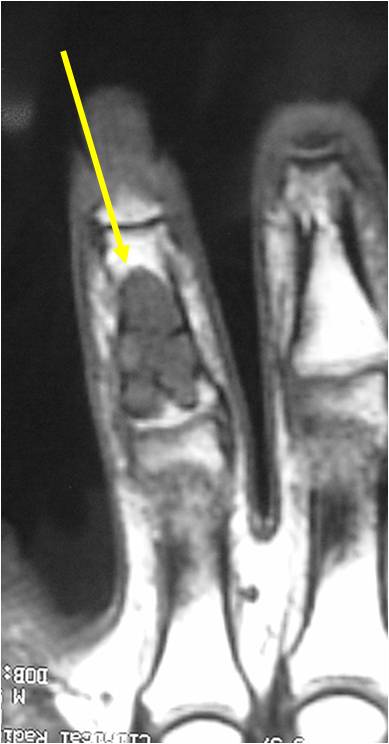

- MRI

- Lobulated margin

- Marked increased intensity long TR images

- Calcified chondroid – low intensity all sequences

MRI:

- Lobulated margin (Lobular Growth Pattern)

- T1 Weighted Images: Intermediate Signal Intensity

- Calcifications will be low signal

- T2 Weighted Images: High Signal Intensity

- High water content shows as high signal on T2 weighted images

- There should never be any cortical destruction nor a soft tissue component. If this exists then the tumor must be a chondrosarcoma.

- Endosteal scalloping and cortical expansion is acceptable for phalangeal tumors. In most benign long bone cartilage tumors there is minimal endosteal scalloping but there should be no cortical expansion nor thickening. There should be no cortical destruction and no soft tissue component associated with an enchondroma. Cortical destruction, periosteal thickening, cortical expansion and a soft tissue component indicates a chondrosarcoma of the long bone.